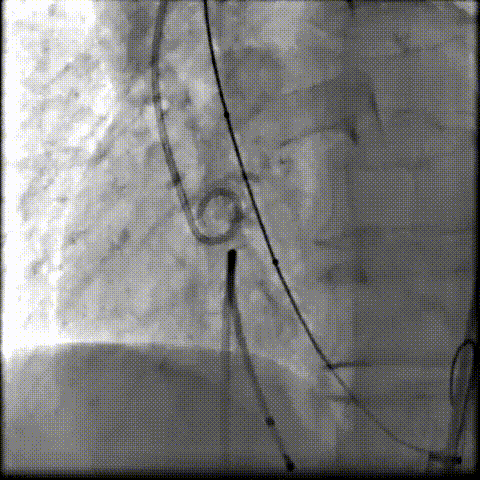

术中影像

根部造影可见返流,23mm球囊预扩张

无窦侧严重钙化及融合影响,

瓣膜(AV29)释放不稳出现反复上跳,2次回收尝试

重新定位释放,

钙化及融合挤压导致瓣膜(AV29)下滑位置偏深

第三次回收重新定位

工作位造影位置良好,完全脱钩释放瓣膜(AV29)

考虑支架腰部挤压,23mm球囊充分后扩后形态良好,

极微量瓣周漏